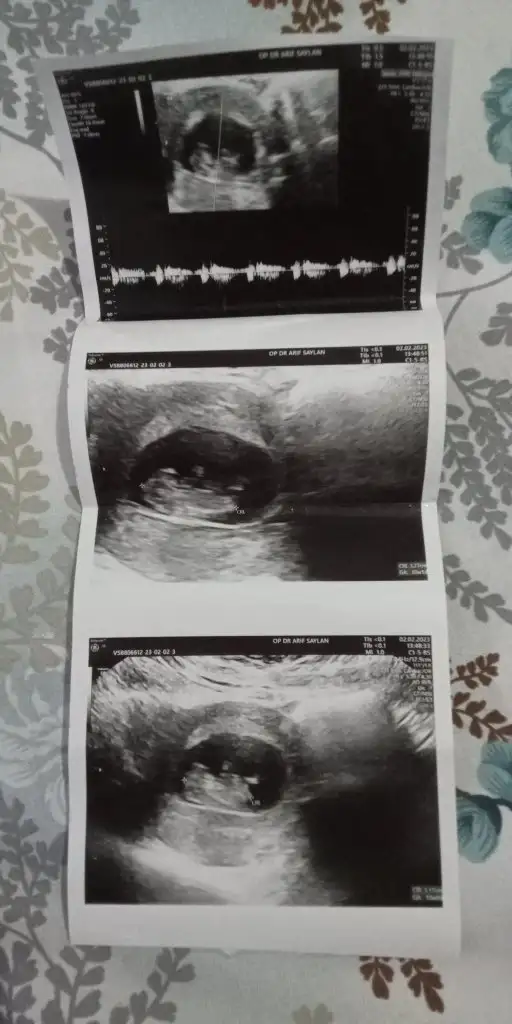

Merhaba millet

Ramzi teorisine göre cinsiyet tahmini yapacagim ilk ultrasyon resminizi atin bakiyim. Eger cinsiyetiniz belliyse hic söylemeeyin bakalm dogru tahmin edebilecekmiyim daha dogrusu ramzi teorisi hakli cikacak mi?

Sizce benim nedir kız gibi dedi ama fikriniz

Eklentiler

• 3C82ED27-2FAC-4521-AC99-75F204A4E937.webp

3C82ED27-2FAC-4521-AC99-75F204A4E937.webp

73,9 KB · Görüntüleme: 95

Kemik yapısı erkeğe benziyor ama ben 6-7-8 haftalık ultrason resmiyle ramzi teorisine göre yorum yapıyorum. Varsa o haftalarda resmi onu atın lütfen☺️